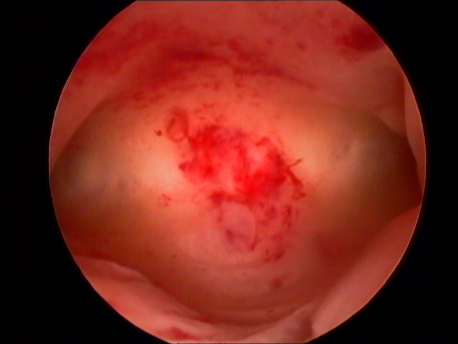

Endoscopy involves placing a small telescope into the human body through tiny incisions (3-5mm). The telescope can be placed into the abdomen via small tubes called ports (laparoscopy) or inside the uterus through the mouth of the uterus or cervix (hysteroscopy).

Various fine and delicate instruments are available through which complicated surgeries can be performed inside the abdomen or the uterus. In fact, endoscopic surgery has become the gold standard of surgery today. Since most of these instruments are being manufactured locally, the cost of endoscopy has also reduced significantly since its advent in the eighties.